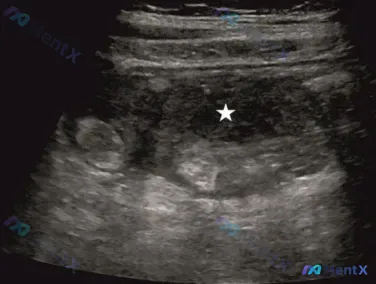

盲肠与子宫之间的低回声包块+少量腹水,第一优先级排查什么?

整理到一份急腹症相关的超声病例资料,影像和临床分析的切入角度有点不一样,放出来讨论一下。 核心超声表现: - 盲肠与子宫之间可探及少量低回声、回声不均的游离腹膜腔积液 - 同一区域另有一处边界相对清晰、以低回声为主、回声不均匀的类圆形/管状异常区域(有疑似靶环征/假肾征表现) - 无典型的后方回声增...